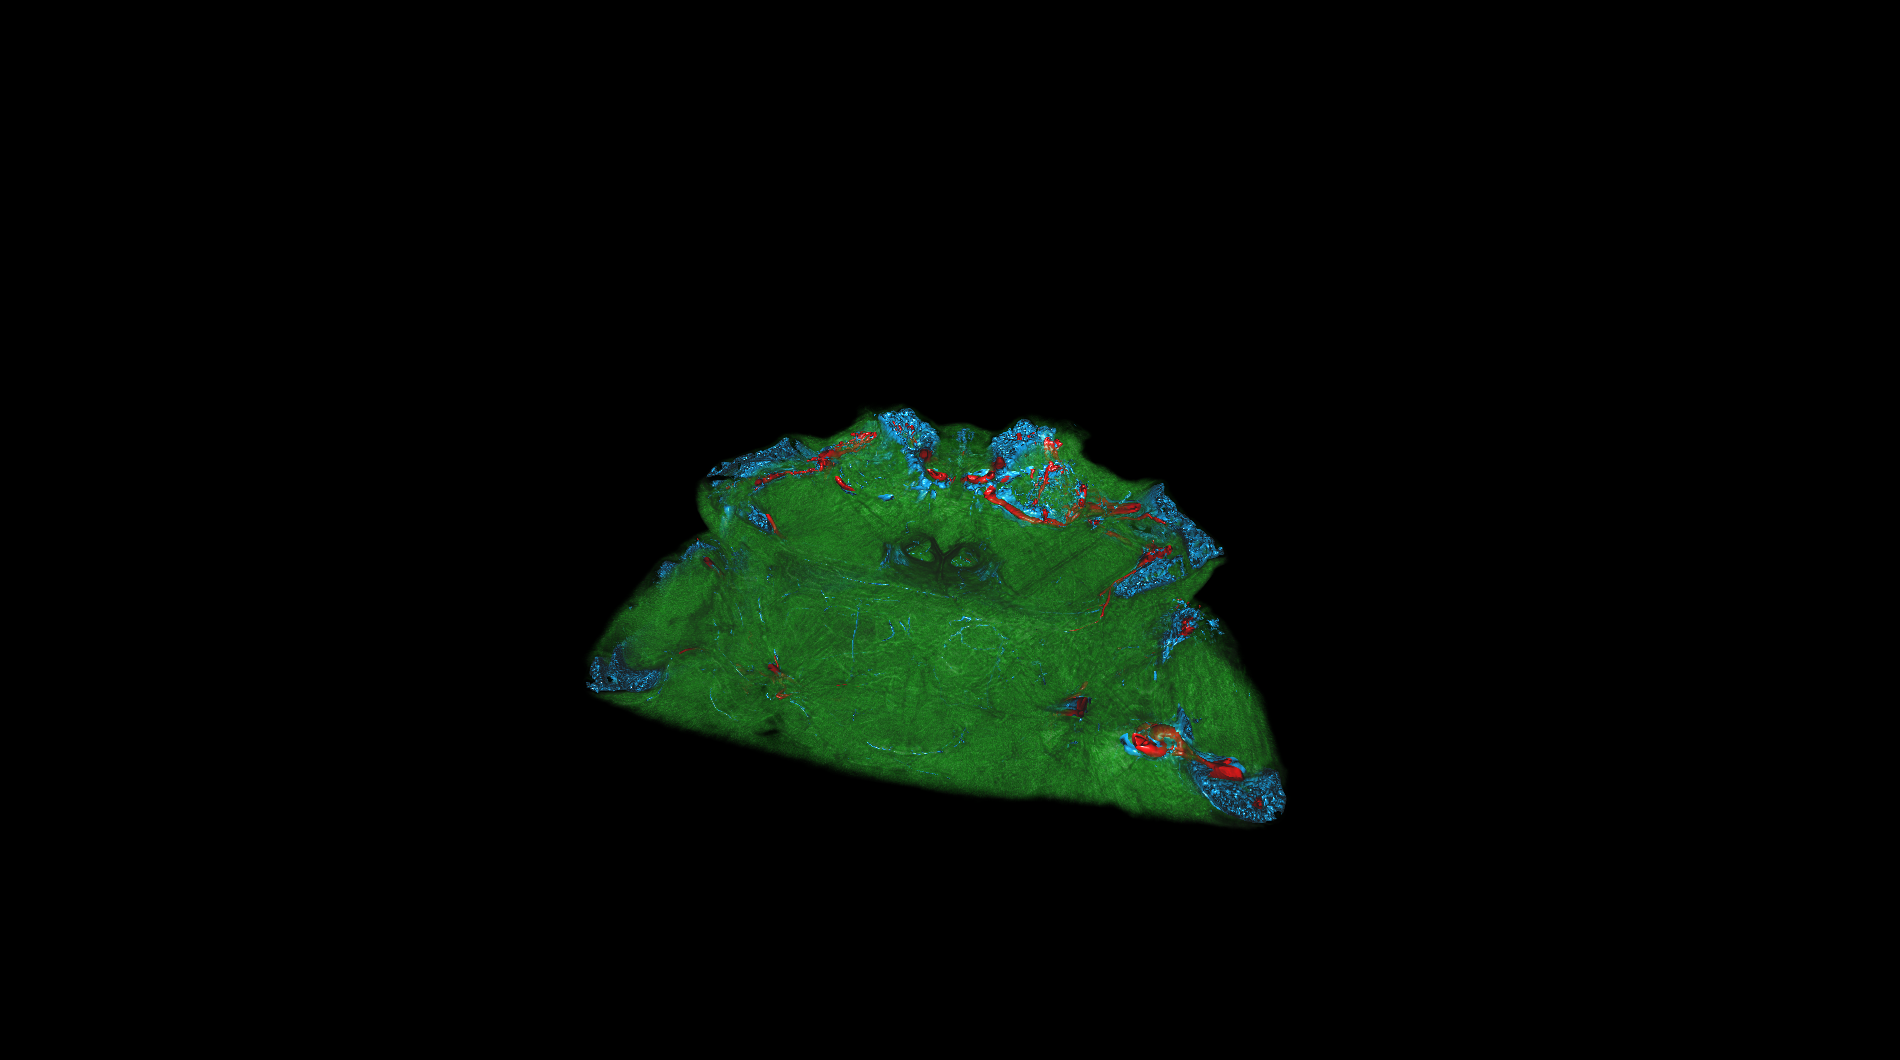

| The medical-04 workload evaluates medical visualization techniques using the Tuvok library and OpenGL API. It features slice rendering and raycasting with 1D and 2D transfer functions, exploring datasets from a beating heart, brain, and alligator. Clipping planes and varying voxel densities test performance in medical imaging workflows, simulating scenarios like MRI and CT analysis. | |||

| Composite Score: | 271.71 | ||

| Graphics Renderer: | RTX 6000 Ada Generation | ||

| Index | Description | Weight | Result (FPS) |

| 1 |

Slice beating heart with 1D transfer

Slice beating heart with 1D transfer

|

10.00 |

906.30

|

| 2 |

Raycasting of a beating heart with 1D transfer

Raycasting of a beating heart with 1D transfer

|

10.00 |

1784.91

|

| 3 |

Slice beetle with 1D transfer

Slice beetle with 1D transfer

|

10.00 |

145.39

|

| 4 |

Raycasting of a beetle with 1D transfer

Raycasting of a beetle with 1D transfer

|

10.00 |

110.86

|

| 5 |

Raycasting of a brain with 2D transfer

Raycasting of a brain with 2D transfer

|

10.00 |

416.83

|

| 6 |

Raycasting of a brain with 2D transfer and clipping plane

Raycasting of a brain with 2D transfer and clipping plane

|

10.00 |

947.32

|

| 7 |

Raycasting of a broken arm with 2D transfer

Raycasting of a broken arm with 2D transfer

|

10.00 |

321.68

|

| 8 |

Raycasting of a broken arm with 2D transfer and clipping plane

Raycasting of a broken arm with 2D transfer and clipping plane

|

10.00 |

499.83

|

| 9 |

Raycasting of an alligator with 2D transfer

Raycasting of an alligator with 2D transfer

|

10.00 |

26.71

|

| 10 |

Raycasting of an alligator with 2D transfer and clipping plane

Raycasting of an alligator with 2D transfer and clipping plane

|

10.00 |

49.60

|